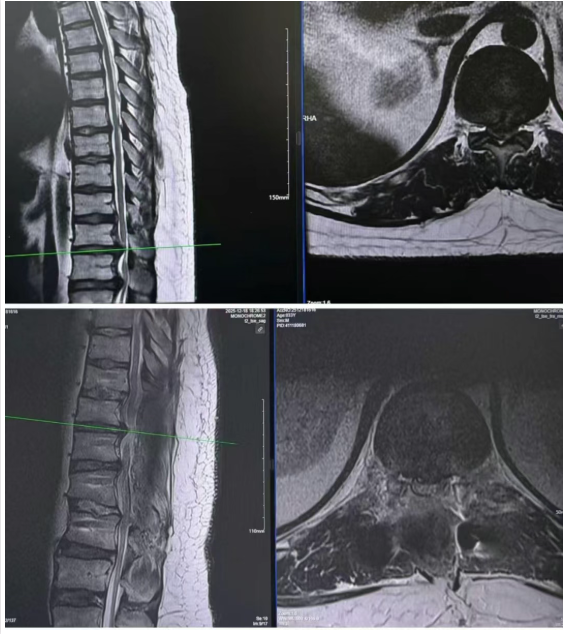

术后MRI见硬膜膨胀,脊髓减压充分

手术中,团队借助神经电生理监测仪全程护航,充分显露椎体后进行精准置钉、椎管减压、椎间盘切除、肋骨截骨、椎体整体前移等关键技术操作,历时4小时顺利完成手术,术后影像显示脊髓减压充分,次日,患者即感觉肢体麻木症状明显缓解。目前,小范术后恢复良好,自己感觉双腿明显轻松了,已能自主行走,下肢神经功能逐步恢复中。